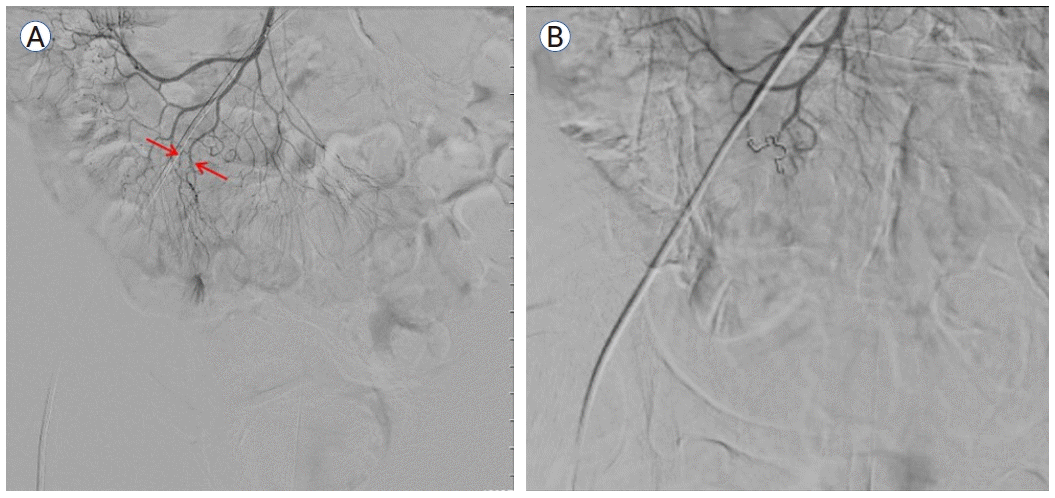

입원 후 시행한 말초 혈액 검사에서 혈색소 수치가 8.4 g/dL로 감소하였으며 이후 이틀간 7.0 g/dL, 5.1 g/dL로 감소하면서 혈변이 지속되어 복용 중인 아스피린, 클로피도그렐을 중단하고 수혈을 진행하였다. 출혈 부위를 찾기 위하여 시행한 상부 위장관 내시경 및 결장경 검사 결과 명확히 출혈을 의심할 만한 부위는 발견되지 않았다. 다음날 추가로 200 g의 혈변이 있어 수혈 후 결장경 검사를 재시행하였으나 출혈 부위를 찾지 못하였다. 이후 복부 출혈 CT 검사를 시행하였고(Fig. 1A) 회장 부위에 출혈 소견이 보여 혈관조영술 검사를 진행하였다(Fig. 1B).

Figure 1.

(A) Transverse contrast-enhanced arterial phase image demonstrate enhancing dot-like structure, which suggested vascular lesions in the ileum. (B) The red arrow indicates extravasation of the contrast dye outlined the ileal mucosa.